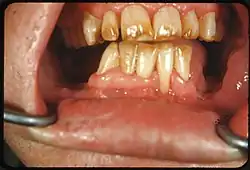

Tooth discoloration is abnormal tooth color, hue or translucency.[1] External discoloration is accumulation of stains on the tooth surface. Internal discoloration is due to absorption of pigment particles into tooth structure.[2][3] Sometimes there are several different co-existent factors responsible for discoloration.[4]

Extrinsic discoloration

Extrinsic discolorations are common and have many different causes.[10] The same range of factors are capable of staining the surface of restorations (e.g., composite fillings, porcelain crowns).[10] Some extrinsic discolorations that are allowed to remain for a long time may become intrinsic.[11]

- Calculus: Neglected plaque eventually calcifies, and leads to formation of a hard deposit on the teeth, especially around the gumline. The color of calculus varies, and may be grey, yellow, black or brown.[12]

- Tobacco: Tar in smoke from tobacco products (and also smokeless tobacco products) tends to form a yellow-brown-black stain around the necks of the teeth above the gumline.[12]